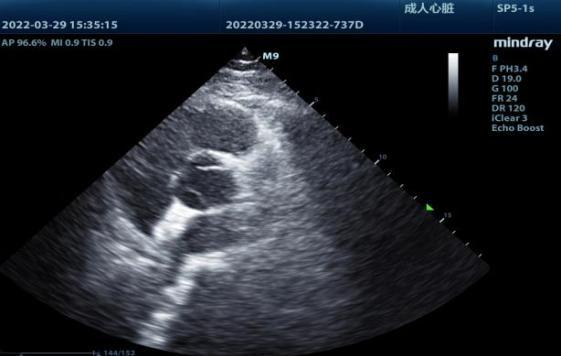

3月29日,我院结构性心脏病诊疗中心介入治疗单元专家团队在东院区介入导管室,为患者成功实施了“卵圆孔封堵术”。局麻下穿刺股静脉,经过未闭卵圆孔建立轨道,将封堵器送达卵圆孔部位嵌入“小孔”阻断异常血液分流,最后由超声进一步检查确认封堵效果,用时不到一小时。

▲术后超声